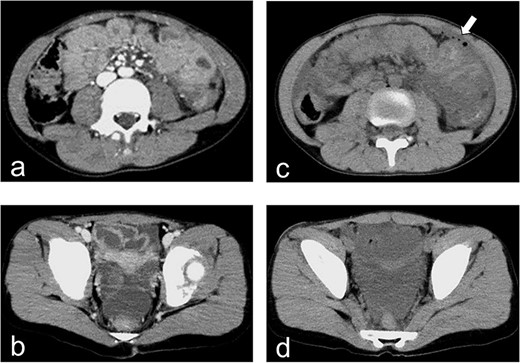

Radiography and CT on hospital day 1. (a, b) Radiography shows fracture of the lumbar spine at L3. (c) CT shows a fracture of the lumbar spine at L3.

A 10-year-old girl was sitting in the back seat of a right-hand drive car, behind the driver, when another car came from the front and bumped into the patient’s car on the right side. The patient was restrained in a three-point seat belt (shoulder and lap belts). She was transferred to our hospital, where she was alert and communicative on arrival. Her chief complaint was abdominal pain. She was 137-cm tall and weighed 30 kg. On presentation, her heart rate was 87 beats/min, her blood pressure was 123/62 mm Hg, her respiratory rate was 20 breaths per minute, her oxygen saturation was 100% and her temperature was 36.7°C. A seat belt sign was observed, with contusions on the forehead and the right iliac region. Her abdomen was tender and she displayed guarding. Focused assessment with ultrasonography for trauma showed a fluid collection in the pelvic cavity. Enhanced computed tomography (CT) demonstrated no free air but confirmed the presence of a fluid collection in the pelvic cavity (Fig. 1a and b). Radiography and CT showed a fracture of the lumbar spine at L3 (Fig. 2a–c).